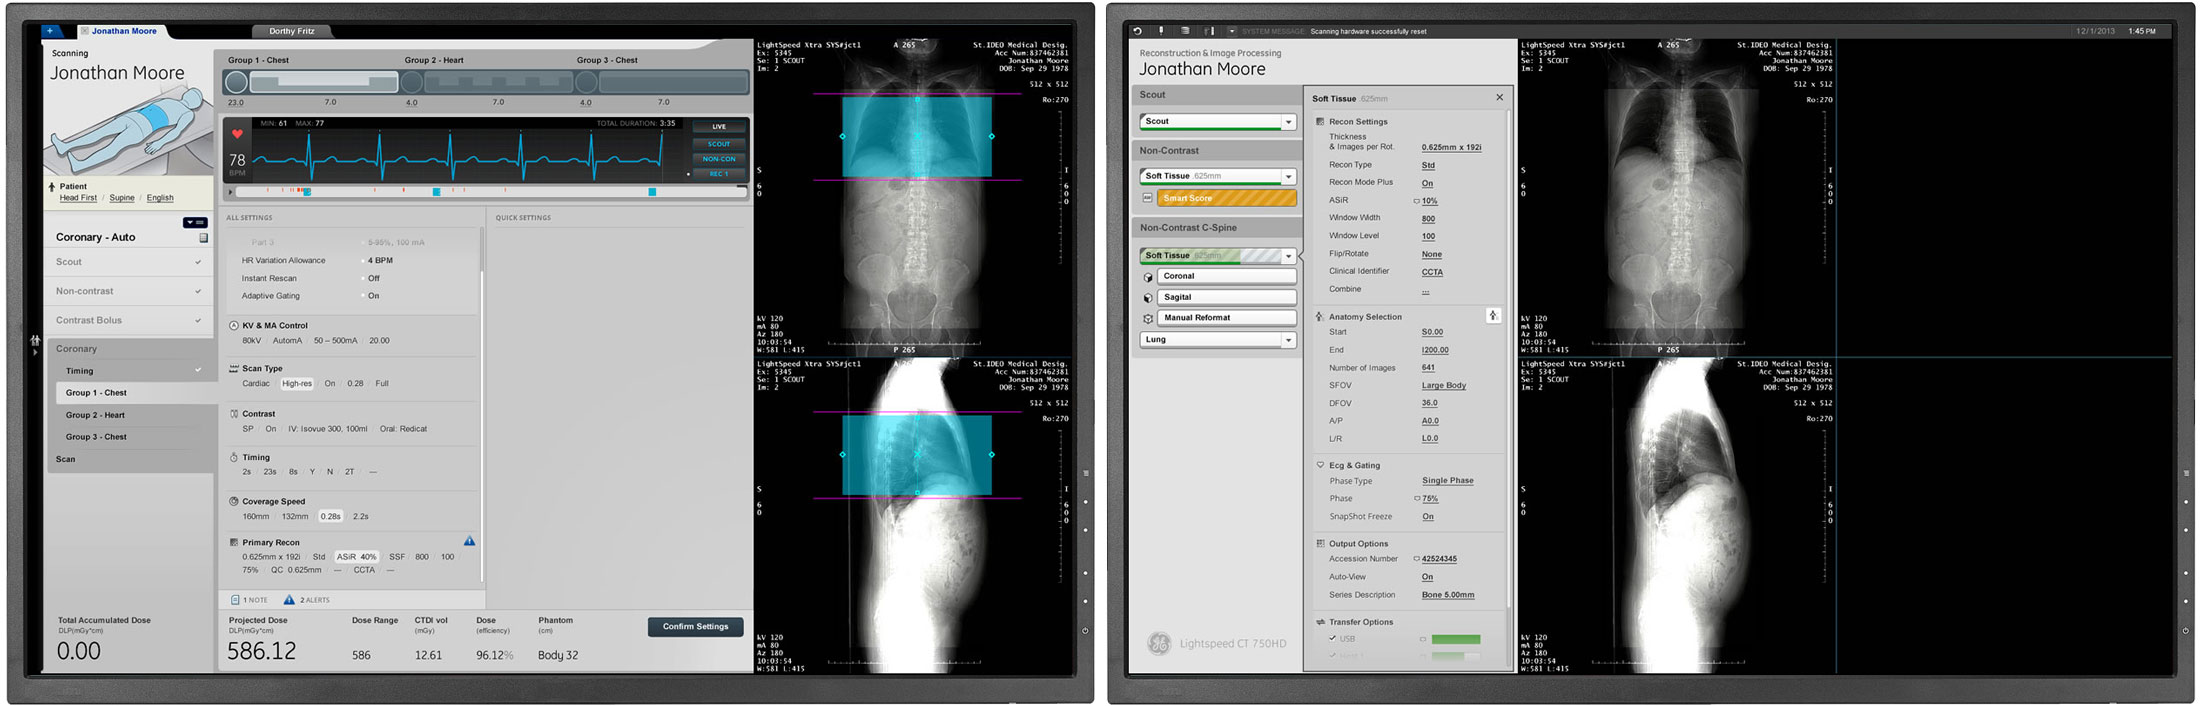

Dual Display

The UI uses two LCD monitors. The left side contains all the scanner settings organized sequentially based on the scanning process. The right side displays visual scan data, results, and renders.